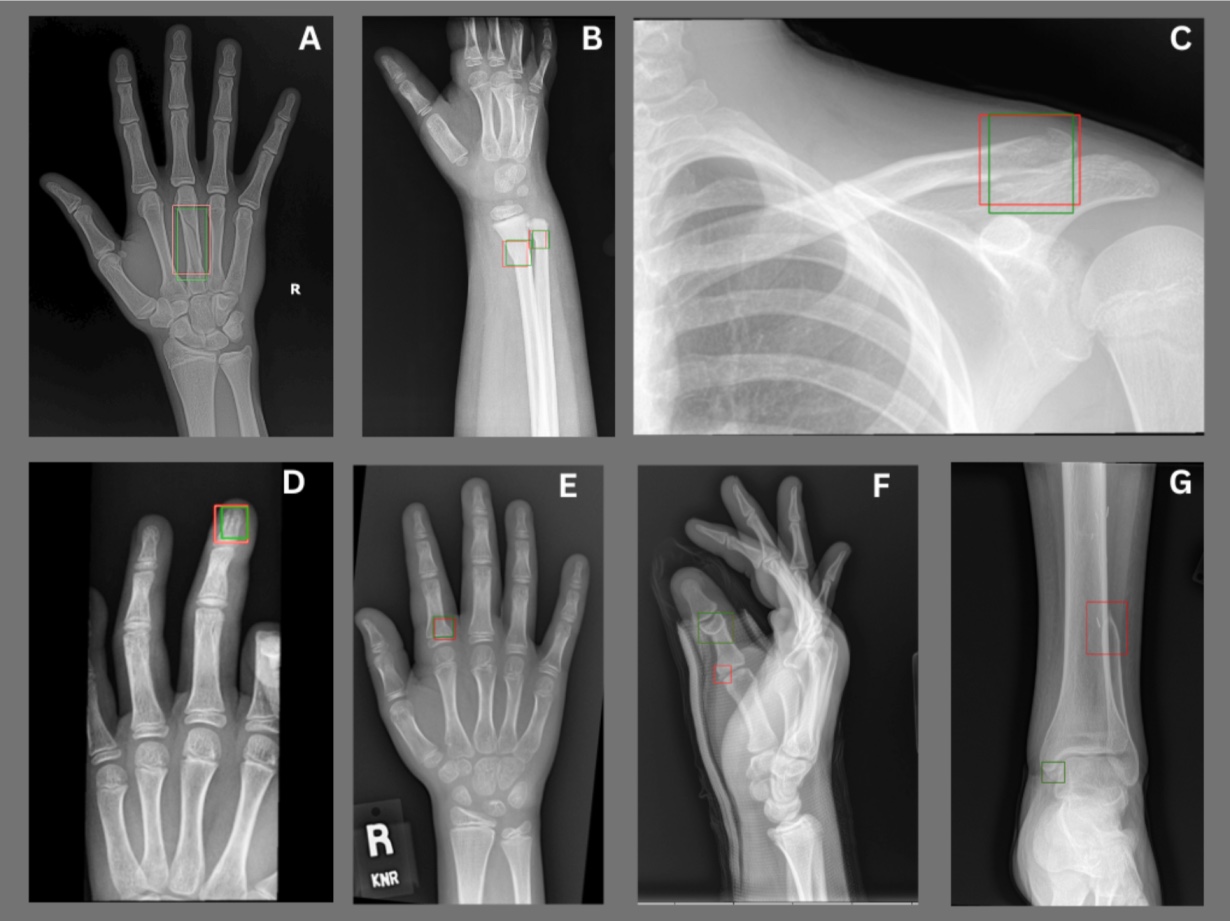

AZmeasure delivers automated characterization of osteo-articular geometries, including lengths and angular positions.

Pathologies Detected

Rayvolve® demonstrated high stand-alone accuracy, aided diagnostic accuracy, and decreased interpretation time.

When extrapolated over an entire population, one can see quickly how using this tool can really help decrease medical errors and healthcare costs.